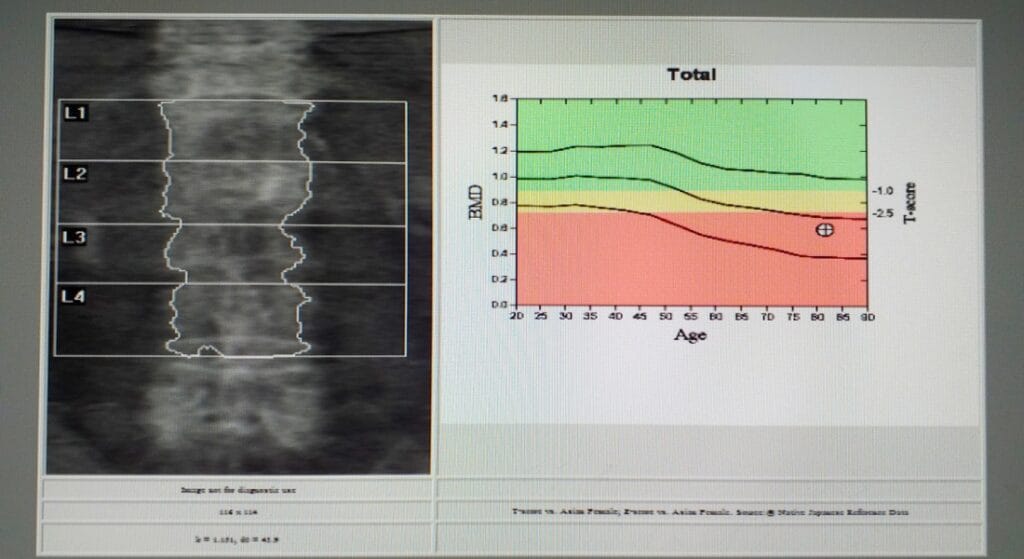

Các chỉ số đo được trong DEXA bao gồm:

- T-score: So sánh mật độ xương của người đo với trung bình của người trưởng thành khỏe mạnh (20–30 tuổi)

- Z-score: So sánh mật độ xương với nhóm người cùng tuổi, cùng giới tính

- BMD (Bone Mineral Density): Giá trị mật độ khoáng xương tuyệt đối, đơn vị g/cm²

- Cột sống thắt lưng (L1–L4): Đây là vùng chịu lực lớn, dễ bị loãng xương và gãy lún khi mật độ xương suy giảm.

Sau khi thực hiện do bằng phương pháp DEXA, người bệnh sẽ nhận được một bảng kết quả với các chỉ số quan trọng:

BMD (Bone Mineral Density): Giá trị tuyệt đối, đơn vị g/cm², phản ánh lượng khoáng chất có trong xương tại vị trí đo

T-score:

- T-score ≥ –1: Mật độ xương bình thường

- T-score từ –1 đến –2,5: Thiếu xương (giảm mật độ xương)

- T-score ≤ –2,5: Loãng xương

Chỉ số này càng thấp thì nguy cơ gãy xương càng cao. Đây là căn cứ chính để chẩn đoán và quyết định điều trị.